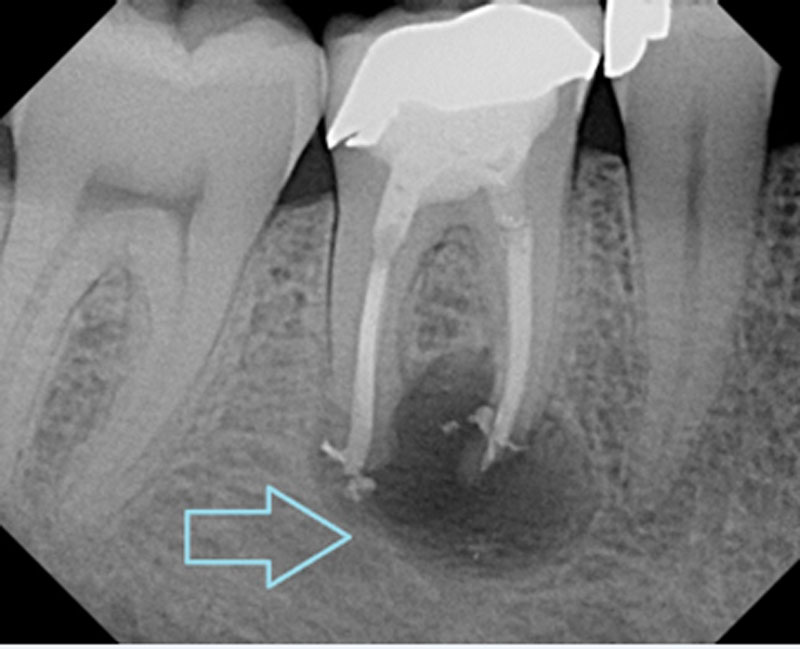

Before treatment, your dentist will take X-rays and perform tests to check for pulp infection, inflammation, or necrosis. These tests may include: Sensitivity Test, Electric Pulp Test (EPT), Swelling Examination, Bite Test.

Apicoectomy (Root-End Surgery)